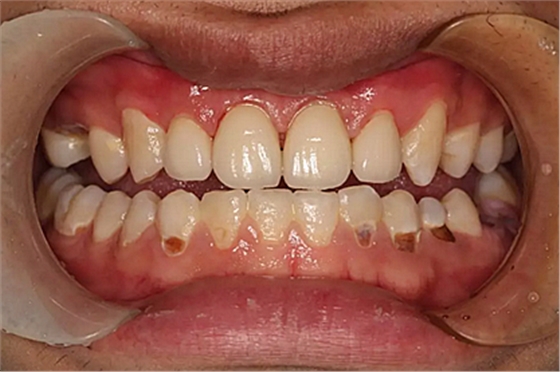

現(xiàn)在剩下的任務就是為我其他的兄弟姐妹們治療了。需要做根管的做根管,需要做冠的做冠,需要樹脂充填的做樹脂充填。前前后后主人帶我們進行了12次的復診,歷時6個月,現(xiàn)在的我們是這樣的

再來看看曾經(jīng)的我們

經(jīng)歷了如此長久的治療,主人應該也是吸取了教訓,或許以后會改了不良的生活習慣,而我們經(jīng)歷了這段涅槃之旅,雖然也煥然一新,重塑了容顏,卻也是歷經(jīng)辛苦,如果主人能好好待我們,其實這樣的痛苦本不需要經(jīng)歷。